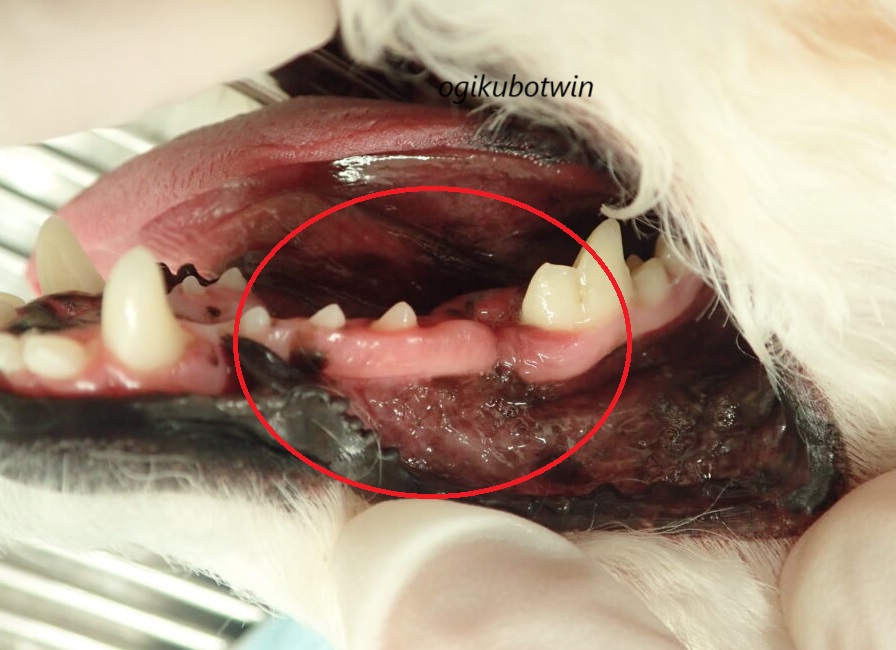

左下顎第四前臼歯(奥歯)と左下顎第一後臼歯(奥歯)の間でかなり歯周病が進行していると思われ、舌側の歯肉が腫れている状況でした。

腫れている部分は歯周病が原因もしくは腫瘍の可能性があると思われます。